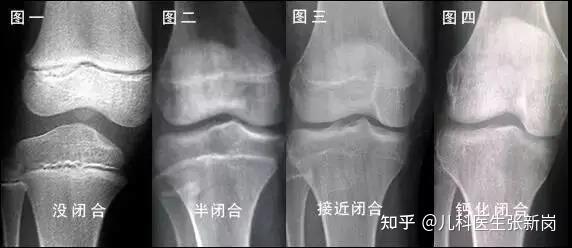

如果过量补钙,可能会造成骨骼提早钙化,加速骨骺线闭合,反而可能导致矮小。

▲骨骺线图